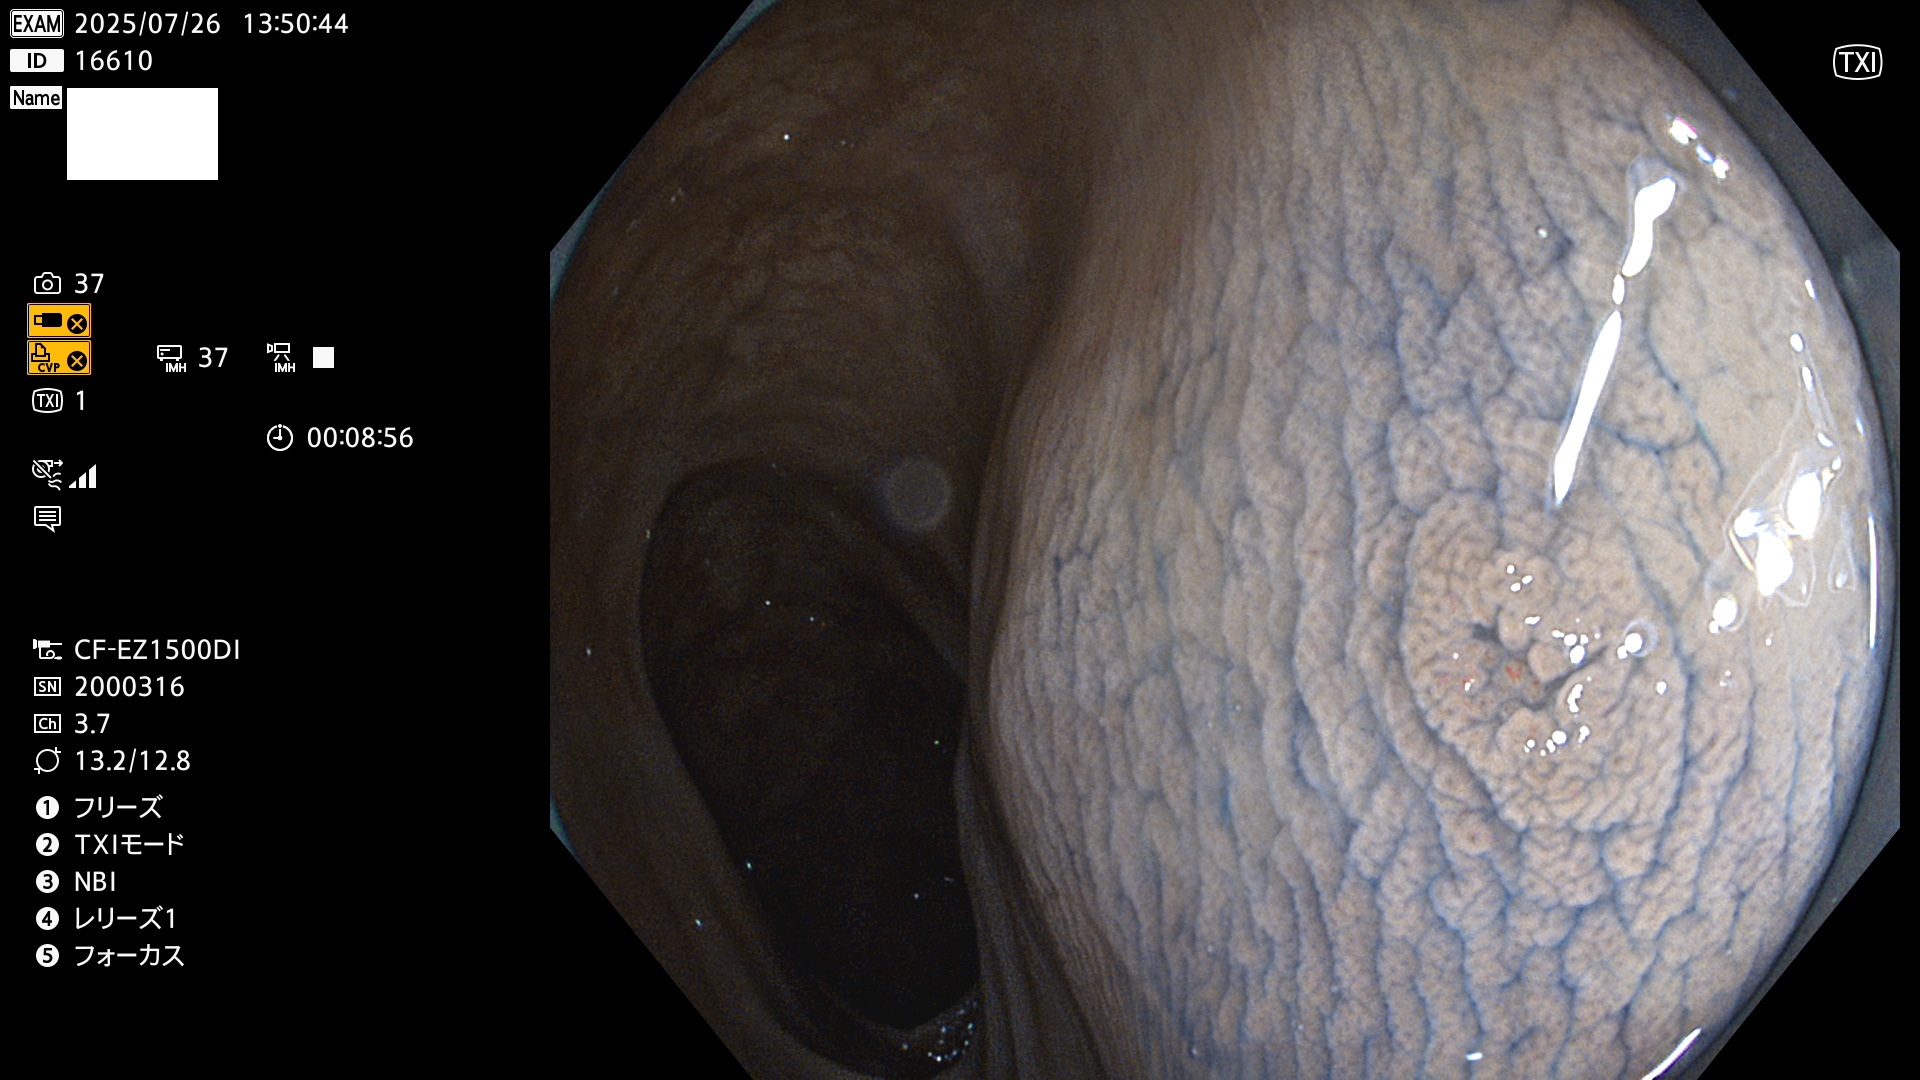

完全に平坦な物をUb、陥凹している物をUcと呼びます。Ubは認識が困難で、Ucはびらん(炎症)と紛らわしいために見落とされやすく、「内視鏡後・大腸癌」の原因になります。

専門的)Uc=De Novo癌? 内視鏡の解像度が低かった時代、このような説もありました。しかし今日の高精度内視鏡では良性の微小なUc型腺腫(APC遺伝子異常の腺腫)が日常的に見つかります。Ucこそが多段階発癌(Adenoma-Carcinoma Sequence)のMain Routeです。

専門的)細胞生物学的Ucの再定義UcをPitと形態学で定義するのは医学的には全く不毛です。Ucの本質はIntraTumor HeterogenityとTumor Dormancyが微小病変に見られる点です。これは早い腫瘍進化=ゲノム不安定性を意味します。そのような病変は隆起型でも形態によらずUcと定義すべきです。なぜなら1年後には陥凹し典型的Uc(最悪の場合NPG癌)になるからです。

2025年7月24日〜7月27日の4日間(40件)15個 (Uc_ADR=15個/40人=38%)